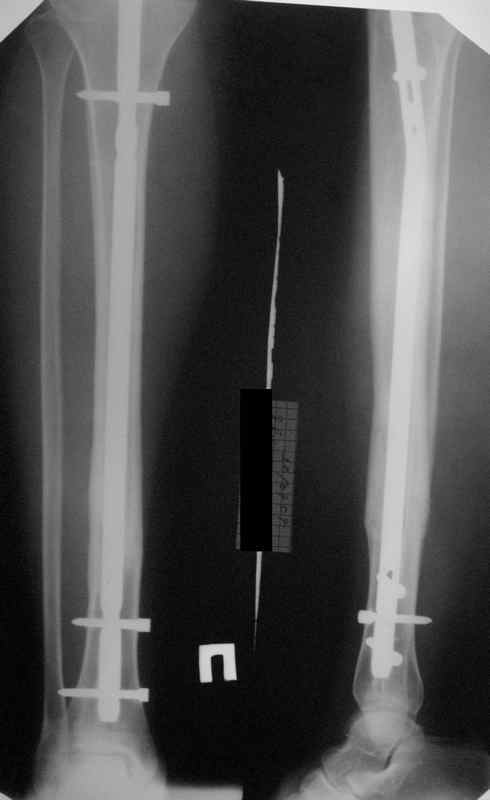

Большинство коллег высказалось против реостеосинтеза и представленные снимки этому подтверждение-данный кососпиральный перелом репонируется идеально только открыто,что при БИОС не так существенно.

Здесь проблема не в идеальности репозиции, а в запасе усталостной прочности. Срастаться там может небыстро, диастазы довольно большие.

И когда еще и отломок короткий, и отверстие совсем рядом, это может привести к перелому стержня. За последние годы у нас было несколько пациентов, оперированных в других учреждениях с

подобным положением отломков, с такими переломами гвздей. И сейчас переделать куда как проще и легче, чем иметь дело со сломанным гвоздем.

Антон, дорогой, важнее вальгуса тут близость верхнего отверстия к перелому и отсутствие уверенности в быстром сращении из-за большого

диастаза.

В Кемпбелле можно прочитать, что Fractures in the distal third of the tibia had the highest frequency of nail breakage.

Вообще, этот вопрос обсуждался давно, и еще в статье R. Bucholz (1987) про переломы гвоздей указывалось, что расстояние от ближайшего отверстия до перелома должно быть не менее 5 см, иначе есть угроза усталостного перелома. По литературе переломы гвоздей в нижней трети

tibia достигают 4,3%.